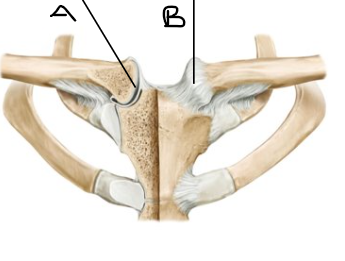

what is letter A? (joint)

sternoclavicular joint

what is letter B? (joint)

sternoclavicular ligament